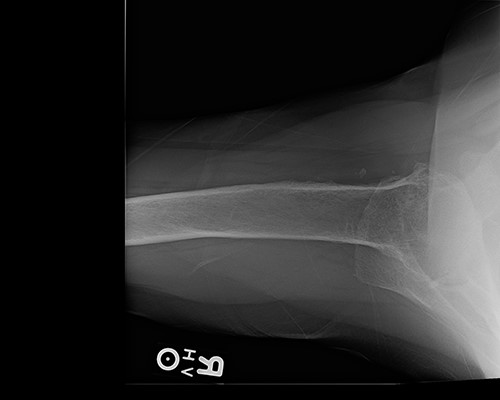

Radiologic imaging revealed bone-on-bone apposition of the glenohumeral joint, with superior humeral head migration consistent with rotator cuff tear arthropathy (Figs 1 and 2).

Grashey view demonstrating glenohumeral osteoarthritis with acromiohumeral space narrowing and superior humeral head migration.